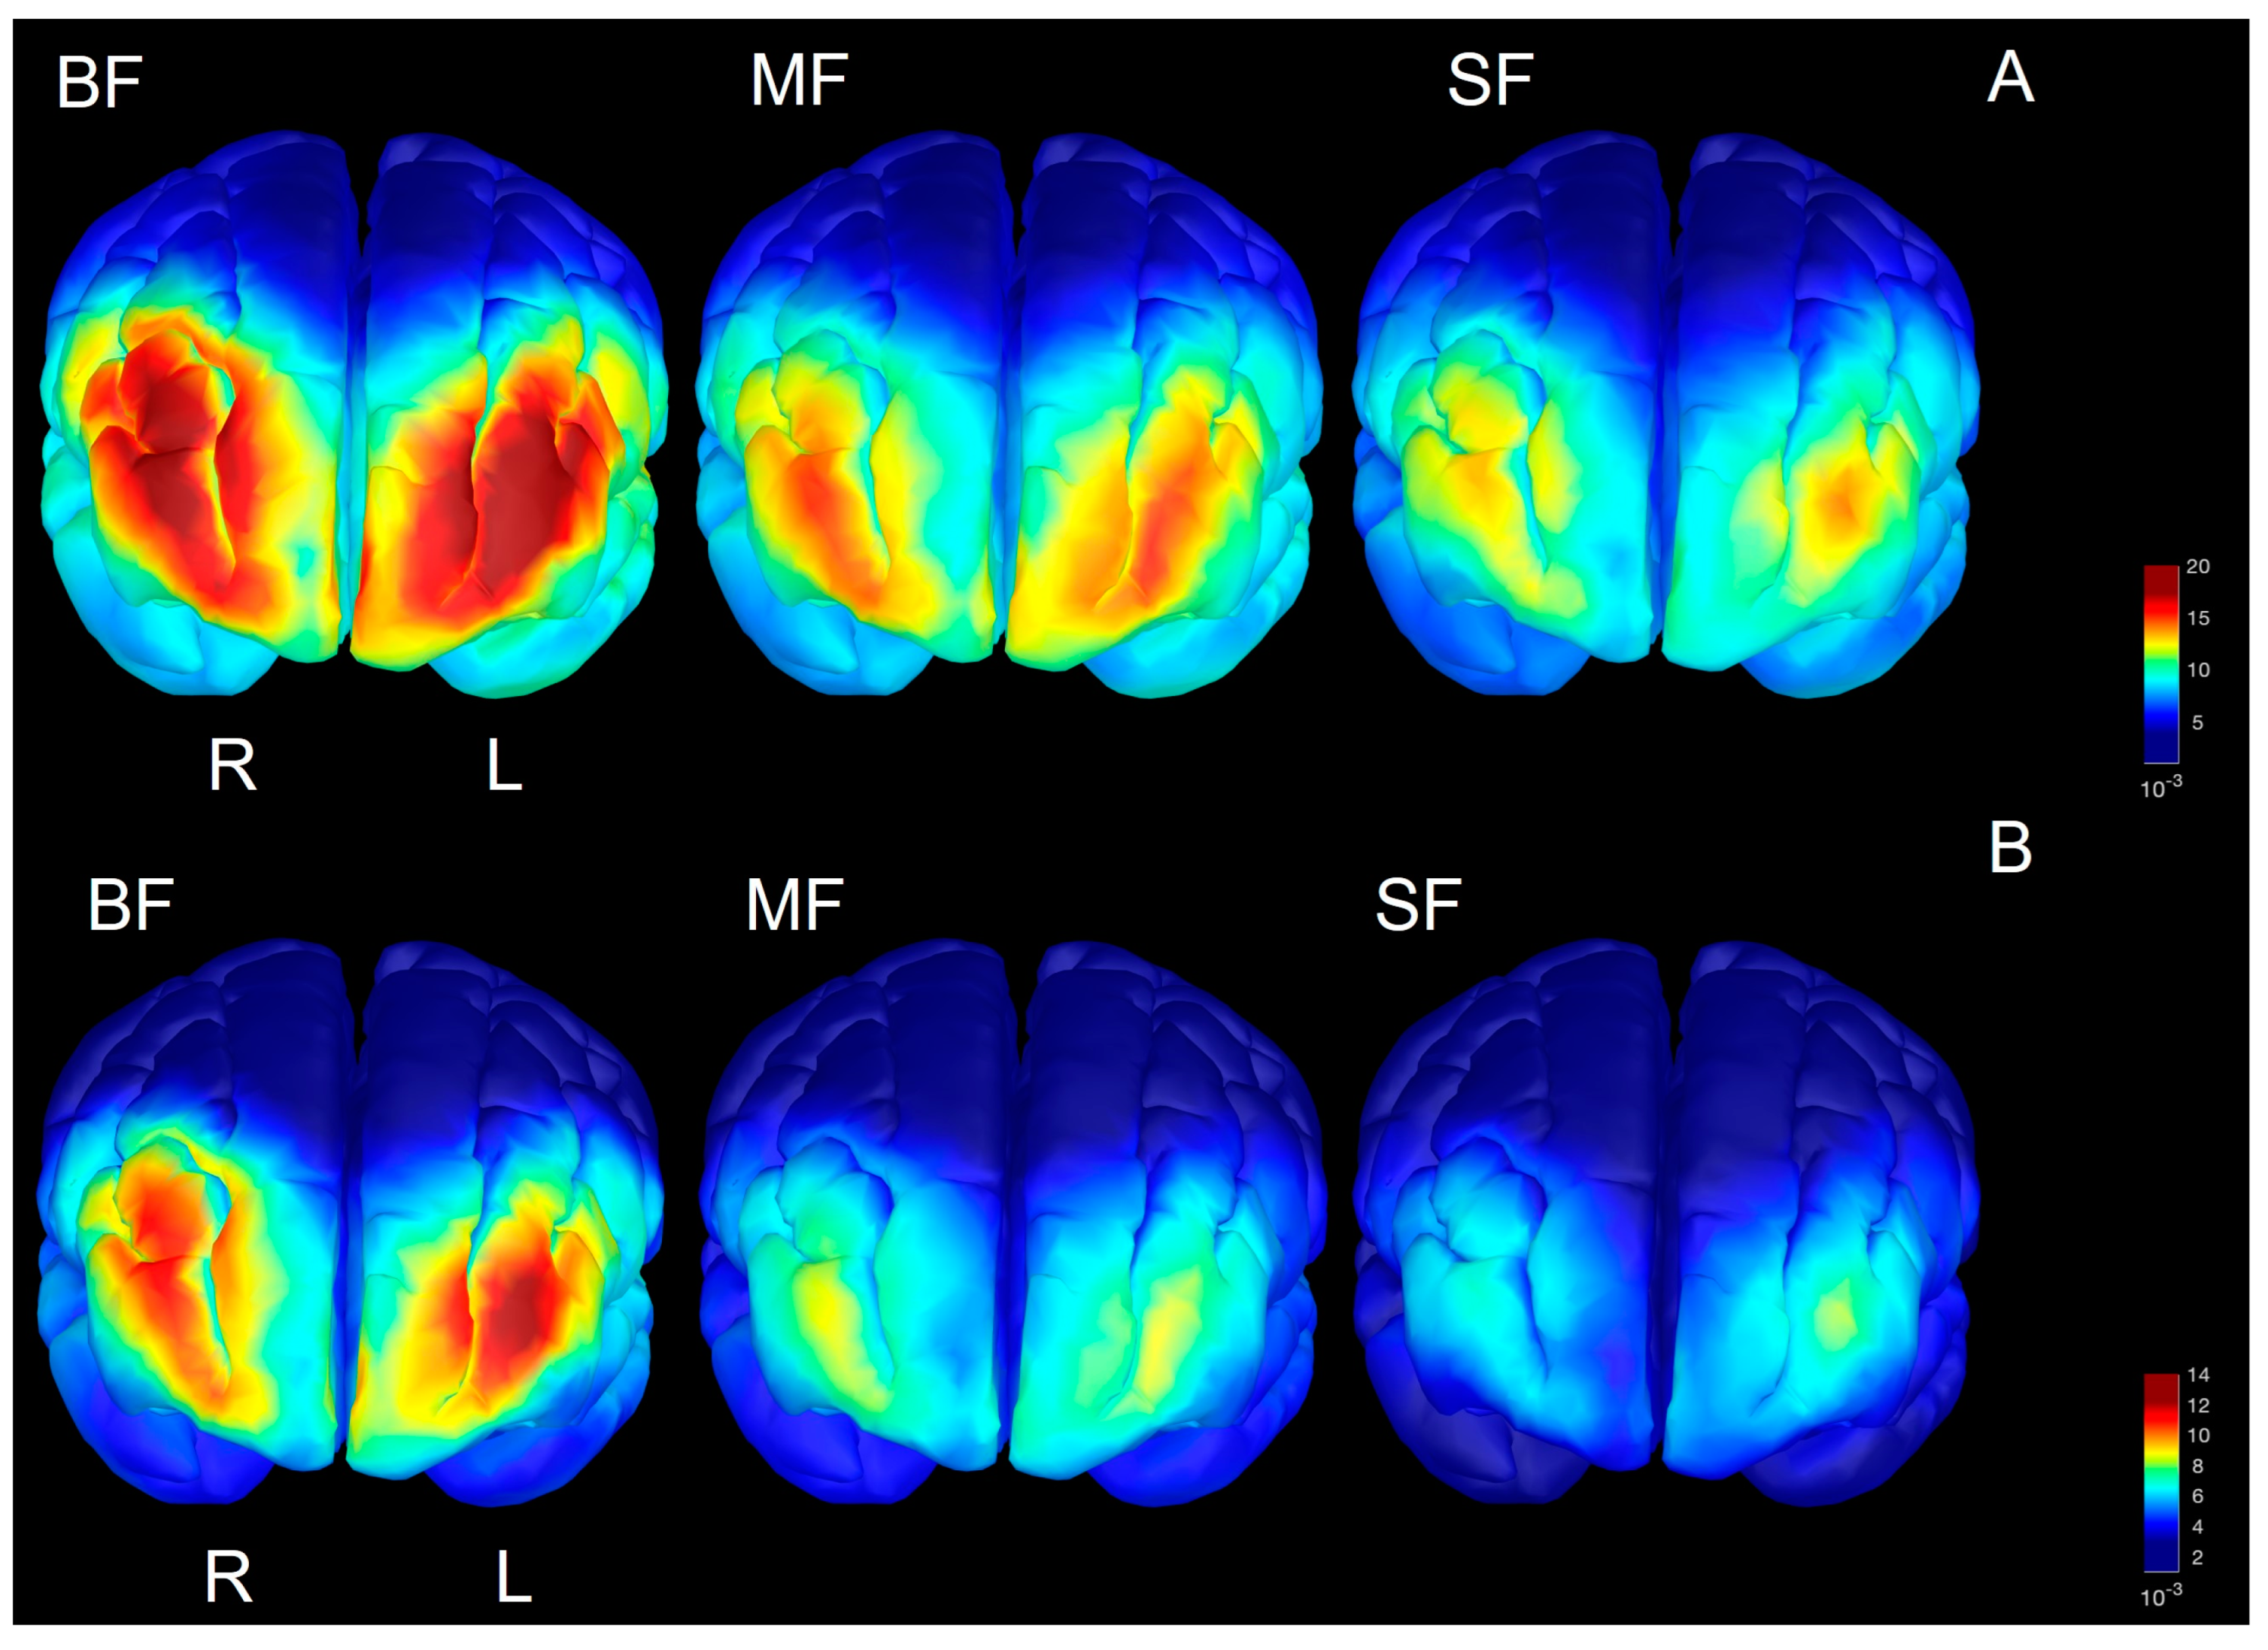

3.4. Spectral Power in Source Space

4.2. Regional Development of Beta/Gamma Defined in Source Space